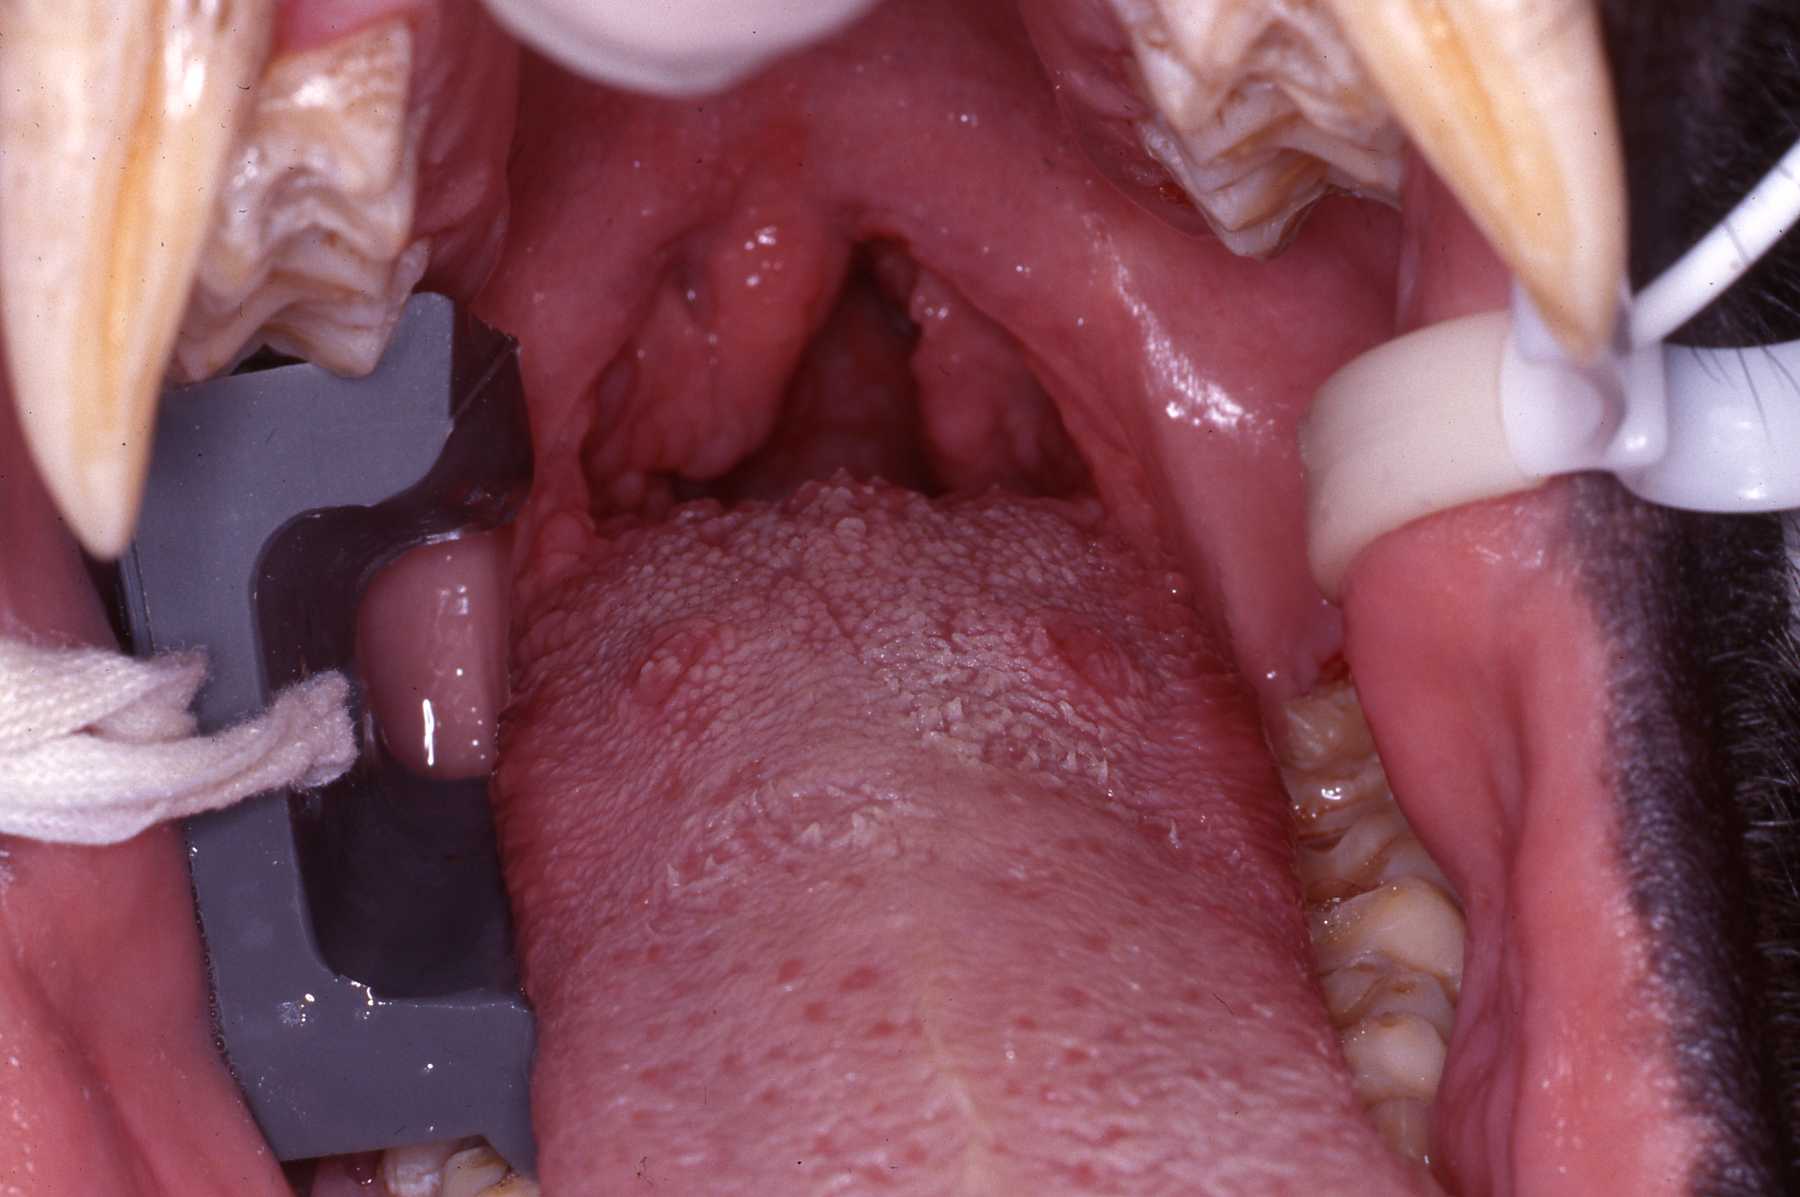

Adult female gorilla “Linda” presented with significant swelling of her right parotid gland. By the day she was sedated and anesthetized for examination and treatment, the infection had burst open through the skin with a purulent discharge. Intraoral exam revealed the inflamed Stensons duct region. Cloudy discharge was also evident in the duct. Dr. Vickie Clyde carefully debrided the gland area and sutured a penrose style drain to the wound. Samples of the draining materia were acquired for culture and with appropriate antibiotic therapy the infection did resolve.

Fistulous chronic drainage tract, found during physical examination, at junction of attached gingiva and buccal mucosa

Enamel erosion throughout dentition due to chronic regurgitation/ingestion behavior